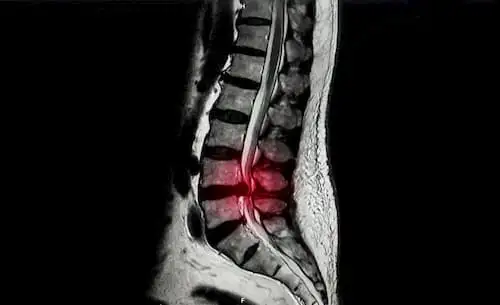

Косий поперековий міжтіловий спондилодез з передньою гвинтовою або задньою педикулярною фіксацією: порівняння методів лікування дегенеративних захворювань поперекового відділу хребта

Дегенеративні захворювання поперекового відділу хребта є серйозною проблемою для охорони здоров'я, що стимулює пошук передових хірургічних підходів.

Дегенеративні захворювання поперекового відділу хребта є серйозною проблемою для охорони здоров'я, що стимулює пошук передових хірургічних підходів. Прикладом перспективного хірургічного підходу є косий поперековий міжтіловий спондилодез (OLIF), але залишається відкритим питання про те, яка з двох технік ефективніша: OLIF з передньою гвинтовою фіксацією (OLIF-AF) або OLIF із задньою педикулярною фіксацією (OLIF-PF). Мета цього дослідження полягала у порівнянні ефективності цих двох технік.